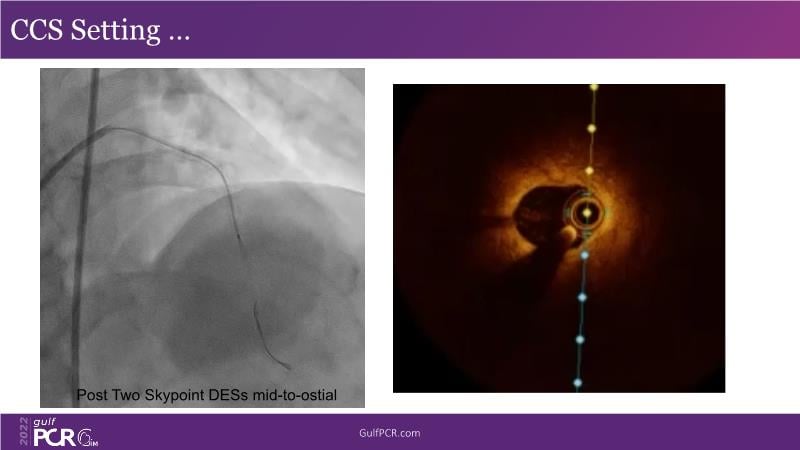

Optimal PCI in patient with long calcified lesion

In this session, follow a LIVE case from the Chest Diseases Hospital in Kuwait and learn what the best strategy is to treat patients who present with a very long calcified coronary artery lesion, as well as how to select the best device and which different types of stents can be used.

- To understand value of intracoronary imaging in patient treatment

- To know the impact of DES platform in the management of a complex patient